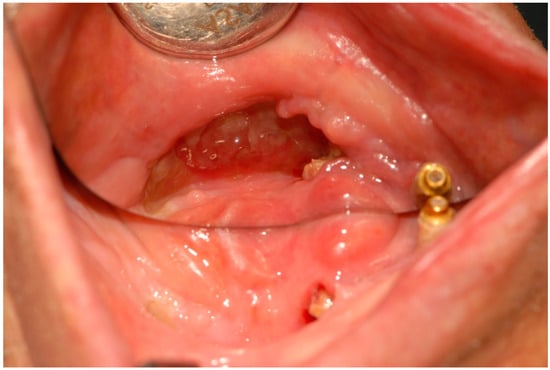

| 0 | First visit (Figure 1), | |||

| biopsy (Figure 2), | PV, peri-implantitis, S/O: gingival malignant tumor | SBCWPV (first) | ||

| start of steroid treatment | ||||

| 4 | Re-curettage, biopsy, antibiotic administration | Bone exposure | PV, socket-healing failure after implant removal, mandibular osteomyelitis, S/O: PIOSCC | SBCWPV (third) |

| 7 | (Figure 3) | Significant enlargement of the lesion due to bone melting at tooth 35 | ||